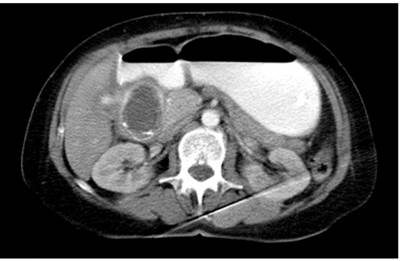

The abdominal CT scan showed intestinal obstruction as an intraluminal image in the first 4.5 x 3 cm duodenal portion (Figure 1 and 2). It was associated with pneumobilia and contrasted bile duct passage. This meets the criteria of Rigler’s triad. In addition, upper digestive tract endoscopy showed dilatation of the gastric chamber secondary to obstruction of the duodenal lumen and an impacted calculus in the duodenal bulb (Figure 3 and 4).